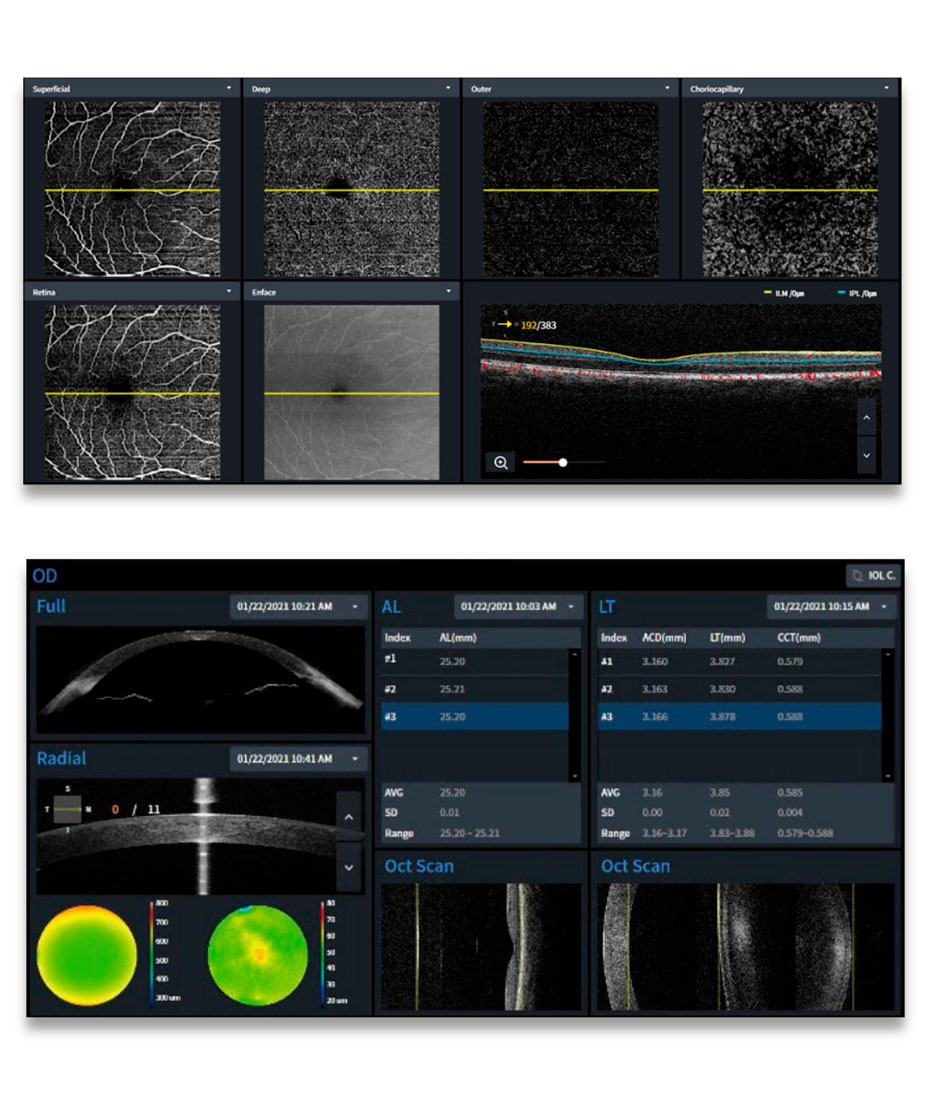

O HOCT-1/1F combina múltiplas modalidades de imagem em um único sistema compacto e intuitivo. Disponível nas versões HOCT-1 (OCT + Segmento Anterior) e HOCT-1F (OCT + Segmento Anterior + Retinografia), o equipamento ainda pode ser configurado com módulos opcionais de Biometria, Topografia e Angio-OCT, tornando-se uma plataforma versátil para clínicas e centros oftalmológicos de alta performance.

Com taxa de varredura de 68.000 A-Scans/s, o HOCT-1/1F entrega imagens de alta definição tanto do segmento posterior quanto anterior, permitindo diagnósticos precisos em retina, glaucoma e córnea. Seu design ergonômico e interface de operação intuitiva garantem praticidade e agilidade no fluxo clínico.

Análise coroidal e vascular com Angio-OCT para detecção de neovascularizações e alterações microvasculares.

- Módulos opcionais: Biometria, Topografia, Angio-OCT

- Análise Angio-OCT: FAZ, densidade vascular, progressão e comparação

- Biometria: Cálculo de LIO com fórmulas e lentes diversas